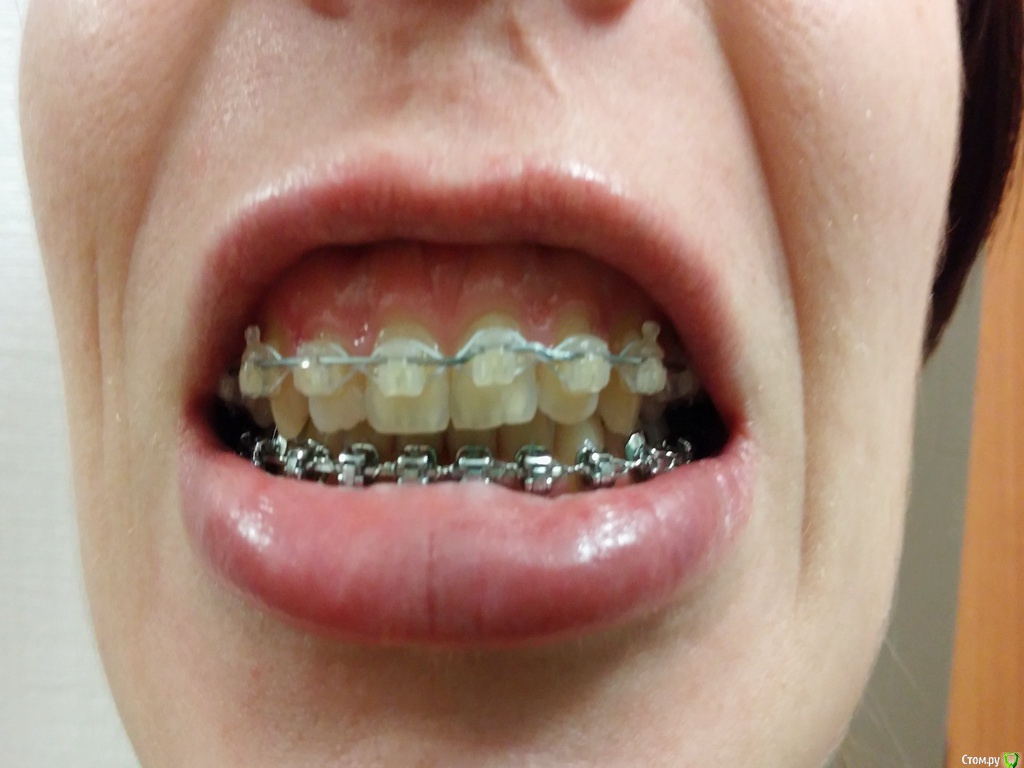

nachik Опубликовано 13 января, 2015 Поделиться Опубликовано 13 января, 2015 Добрый день. Ношу брекеты с октября 2012 года (2 года 4 месяца). Цель установки: освободить место под дальнейшую имплантацию. Вставлять имплант при кормлении грудью не советует врач по причине того, что возможно придется пить антибиотики. Нижняя челюсть зашинирована в ноябре 2013 года, верхняя – в ноябре 2014 года.Мои вопросы:1.Возможно ли мне снять брекеты сейчас и носить несъемные ретейнеры и съемные (или капы), а поставить импланты уже после завершения кормления грудью? Мой ортодонт предлагает снять систему только после установки зубов, а это еще год-полтора. 2. Можно ли изменить ситуацию с верхними единичками? Ортодонт говорит, что один зуб стерся неравномерно, вот по-этому так и останется.Снимок до установки. Фото сейчас. Ссылка на комментарий

orthophil Опубликовано 17 января, 2015 Поделиться Опубликовано 17 января, 2015 По фотографии не понятна ситуация вообще и с "единичками" в частности. Хотелось бы более качественные фото без искажений.По поводу снятия брекетов сначала и имплантации через определенный прмежуток времени не вижу никаких проблем, только необходимо изготовить п-образный частичный несъемный ретейнер для стабилизации зубов рядом с отсутствующим зубом/зубами для предотвращения их смещения. Так для гигиены будет прще и вообще приятнее. Ссылка на комментарий

nachik Опубликовано 20 января, 2015 Автор Поделиться Опубликовано 20 января, 2015 Спасибо за ответ. А съемные ретейнеры или капы нужно будет носить? Прикрепляю новые фотографии. Ссылка на комментарий

orthophil Опубликовано 20 января, 2015 Поделиться Опубликовано 20 января, 2015 Спасибо за ответ. А съемные ретейнеры или капы нужно будет носить? Это зависит от выбора Вашего врача, но возможны варианты при обсуждении. Немного смущает смещение центральной линии на нижней челюсти. Ссылка на комментарий